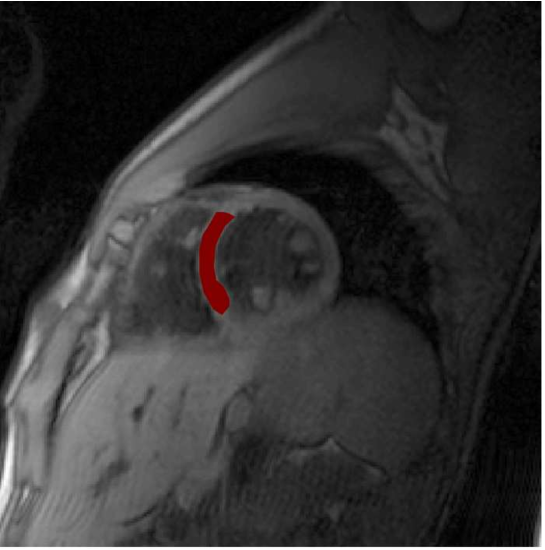

Im menschlichen Myokard haben die Kapillaren einen Radius von RC=2,75μmsubscript𝑅C275𝜇mR_{\text{C}}=2,\!75\,\mu\text{m} und das regionale Blutvolumenverhältnis beträgt etwa η=0,084𝜂0084\eta=0,\!084 [6]. Daraus ergibt sich ein zylinderförmiges Versorgungsgebiet mit einem Radius von R=9,5μm𝑅95𝜇mR=9,\!5\,\mu\text{m}. In Abb. 4 ist der aus der Physiologie bekannte Krogh-Zylinder zur Beschreibung des Atemgaswechsels zwischen dem Blut und dem Gewebe dargestellt. Der Sauerstoffpartialdruck sinkt sowohl senkrecht zur Kapillare mit zunehmender Entfernung von dieser als auch entlang der Kapillare in Richtung des venösen Endes. Kapillarferne Zellen am venösen Ende des Krogh-Zylinders werden am schlechtesten mit Sauerstoff versorgt und sind am ersten von Hypoxie bedroht (rotes Rechteck in Abb. 4). Zur Beschreibung des MR-Signalverhaltens interessiert in dieser Arbeit allerdings nicht der Sauerstoffpartialdruck im Versorgungszylinder, sondern die Dephasierung der Spins, die um die Kapillare diffundieren. Deshalb wird dieser Versorgungszylinder bei der Untersuchung des MR-Signals auch als Dephasierungszylinder bezeichnet. Die Diffusion der signalgebenden Protonen findet im Raum zwischen der Kapillare und dem umgebenden Zylinder im Gewebe mit dem Diffusionskoeffizienten D=1μm2ms1𝐷1𝜇superscriptm2superscriptms1D=1\,\mu\text{m}^{2}\text{ms}^{-1} statt [6] (siehe Abb. 4). Der Diffusionsprozess wird durch die charakteristische Korrelationszeit

Refer to caption

Abbildung 4: Links: Versorgungsbereich einer Kapillare mit dem entsprechenden Sauerstoffpartialdruck (nach [13]). Mitte: Dephasierungsgebiet, in dem die Diffusion (rote Trajektorie) und die Dephasierung stattfinden. Rechts: Querschnitt durch Kapillare und Dephasierungsgebiet mit Polarkoordinaten.